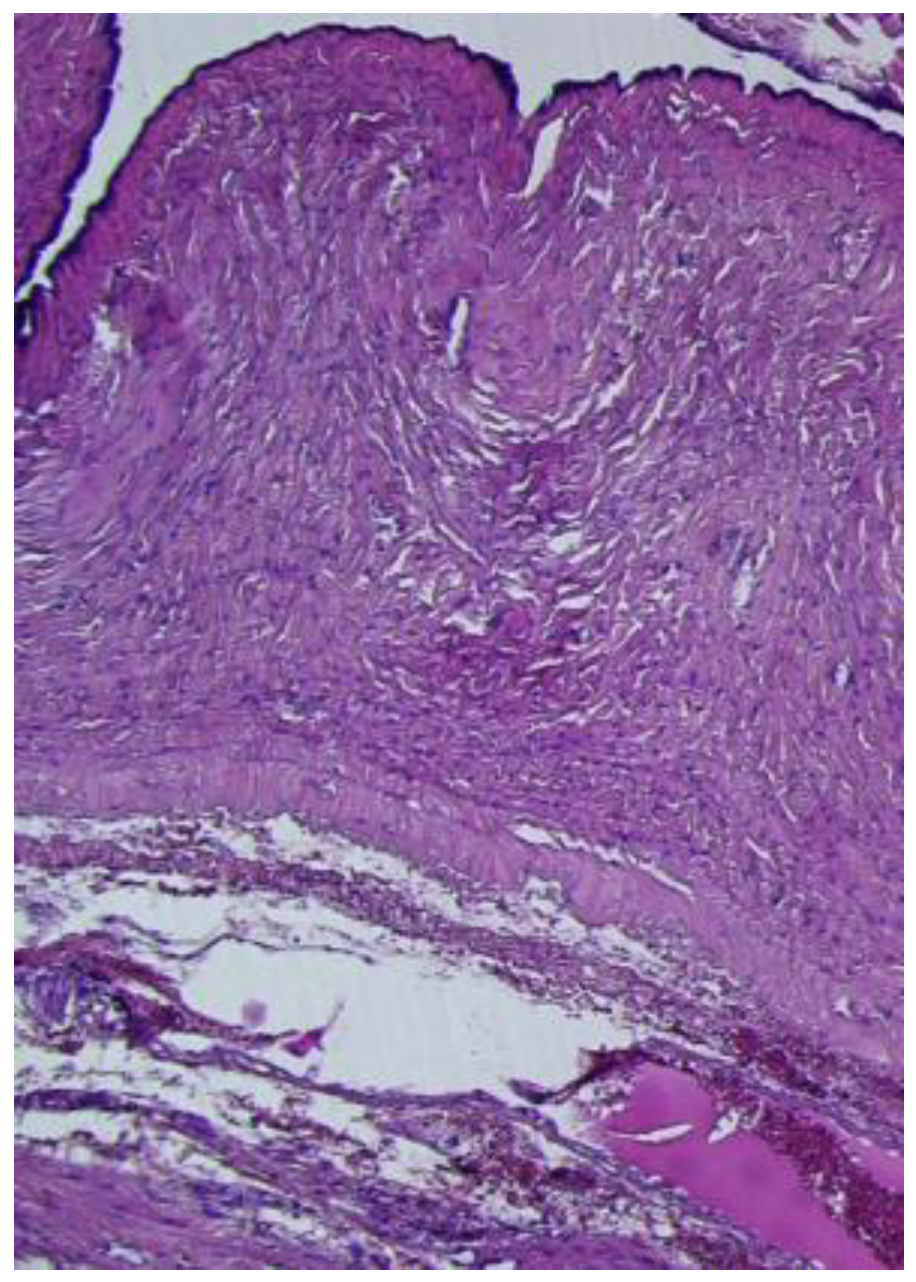

The cyst had a morphological connection with the fallopian tube (Figure 6), which presented a mucosa lined by a simple columnar epithelium with focal stratification.

Figure 6. Paratubal cyst, lined by a simple, flat, cuboidal to columnar epithelium, in morphological continuity with the fallopian tube wall (HE ×10).